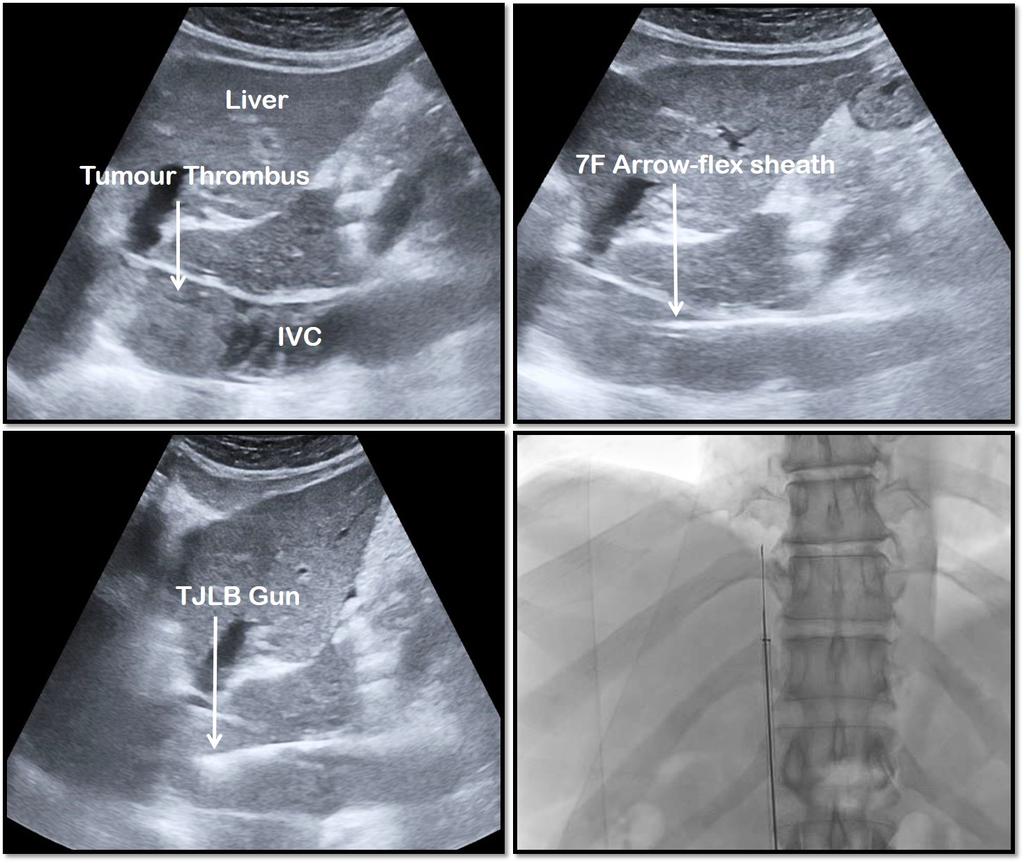

This middle aged man came with abdominal discomfort and was found to have a large tumor inside the liver that had spread into the veins inside the liver (hepatic veins) and also into the large vein that drains..

2/..into the heart (called IVC or inferior vena cava).

Without a biopsy diagnosis of the type of cancer, oncology/radiotherapy would not proceed with treatment plans

The bleeding tests were abnormal and there was mild fluid in abdomen of this patient - this meant that we..

3/..could not perform a direct biopsy of the tumor in the liver due to high risk of bleeding

Without a biopsy diagnosis, we could not proceed with treatment plans

So @SRajesh_IR, our lead Interventional Radiologist, does something adventurous. The family wanted a diagnosis..

4/..to at least understand what was hurting the patient.

Dr Rajesh approaches the cancer filled clots in the large vein through a catheter placed through another vein in the leg and fires the biopsy gun through the middle of the tumor filled vein

A risky procedure, that could..

5/..tear the large blood vessel that could instantly kill the patient or dislodge the tumor into the heart - but with precision and skill, clots were retrieved for pathologist to review

& it showed hepatocellular carcinoma, a primary cancer of liver arising from liver cells..

6/..that was clogging the big vein and swarming the heart chambers.